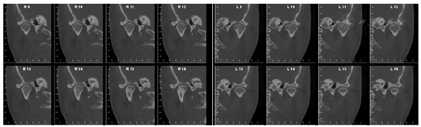

(1)正面观面上1/3比例稍短,面下1/3高度正常;颏部右偏2 mm;上下颌牙齿中线与面中线不一致;上颌中线右偏3 mm;下颌中线右偏2 mm;侧貌突;双侧颞下颌关节区无压痛及弹响,开口度及开口型未见异常;11、21根尖区瘘管;右侧尖牙、磨牙关系远中关系,左侧尖牙、磨牙远中关系;覆盖Ⅲ°,覆合Ⅰ°;上前牙牙轴均向右侧倾斜,15、16联冠,上颌间隙6 mm,37牙列缺失,下颌拥挤度3.5 mm(图1,图2)。(2)牙周会诊检查:口腔卫生欠佳,菌斑指数PLI:2~3,牙石(++~+++),色素(+~++)。全口牙龈色暗红,牙龈厚钝,质地松软,牙龈无剥削。探诊深度PD>3 mm,附着丧失AL+,牙龈出血指数BI:2~4,BOP(+)。根分叉病变FI:Ⅱ,11、22松动Ⅲ°,23松动Ⅱ°,12、36~41松动Ⅰ°(图3)。

1.牙周治疗:拍摄X线曲面断片,FloridaProbe牙周检查;全口超声龈上洁治,抛光,口腔卫生宣教;11根据牙周治疗恢复情况再进一步治疗;2周后,上颌及下颌前牙牙周内窥镜超声及Gracey刮治器龈下刮治,根面平整;2周后,评价上颌及下颌前牙牙周情况,下颌双侧后牙牙周内窥镜超声及Gracey刮治器龈下刮治,根面平整;1个月后,FloridaProbe牙周检查,全口超声及Gracey刮治器龈下刮治,根面平整;1个月之后,试保留32~42,32~42牙周翻瓣成形术,期间完成11根管治疗后进行根尖手术;1个月之后,再次评价下颌前牙牙周情况,全口龈上洁治,抛光;1个月复查,拍摄X线曲面断层片,FloridaProbe牙周检查,全口超声龈上洁治,抛光;3个月复查,拍摄X线曲面断层片,FloridaProbe牙周检查,全口龈上洁治,抛光;患者牙周状态稳定,牙龈颜色正常,无活动性炎症出现,可行正畸治疗。正畸期间,每3个月牙周复诊。

经过矫正前的牙周系统治疗以及22个月的矫正加稳定并联合矫治期间定期的牙周维护治疗,矫治结束后患者上下牙列牙齿排列整齐,建立了正常的覆牙合覆盖,维持了双侧磨牙、尖牙咬合关系,未有咬合干扰点,达到稳定的咬合关系。同时,牙周袋并未加深,11瘘管愈合(图2),全口牙龈颜色正常,牙周组织无活动性炎症出现,另外,患者口内治疗前多颗松动的牙齿,其松动度也有明显的改善,例如治疗前11、22松动Ⅲ°,23松动Ⅱ°,12、36~41松动Ⅰ°。治疗后11、22松动Ⅰ°,其余牙齿稳定无松动现象。X线表现(图9)治疗后牙槽骨吸收停止且23~26近远中,36远中以及27近中等部位均有少量牙槽骨再生,骨白线连续性亦有增加,下前牙区牙槽骨高度有少量增加。关节矢状面、冠状面保持稳定,FloridaProbe牙周检查最终探诊深度普遍降至1~3 mm。X线头影测量前后对比以及重叠图可见上前牙内收较明显,下切牙压低有效,侧貌突度明显改善(图10,图11,图12,图13,图14)。